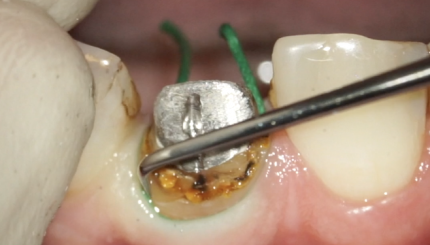

14 ,15,36,46 ОТТИСКИ С ЗУБОВ И ИМПЛАНТАТА